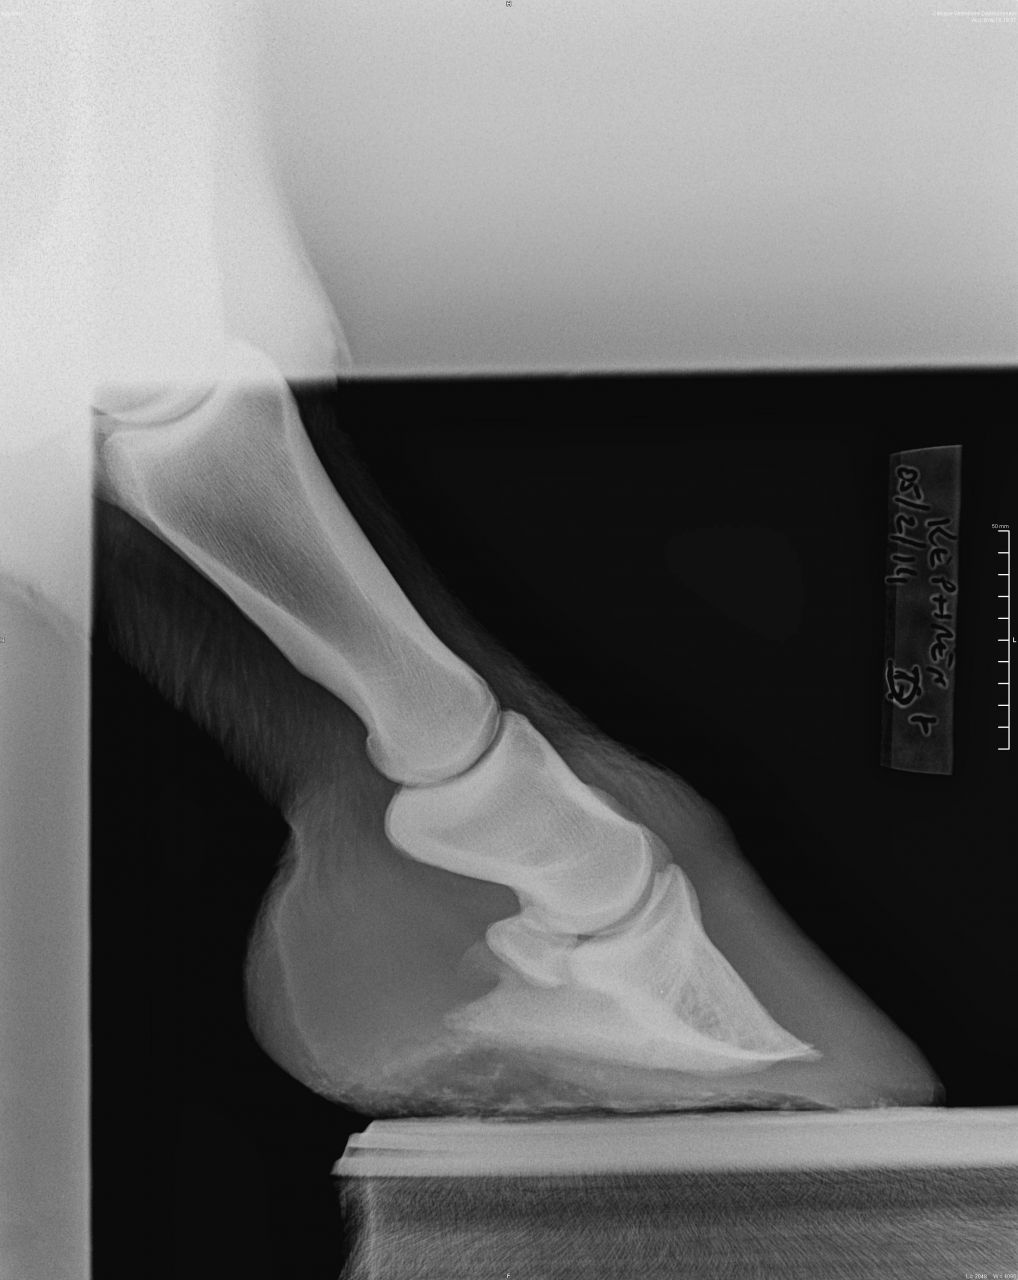

DéconnectéDire merci | Sur la radio de 2011, on voit déjà que le bord solaire de P3 est irrégulier, voir possiblement fracturé sur le côté droit. Je ne vois pas de bascule plus que cela de P3. Dommage qu'il n'y ait pas de nouvelle vue récente du bord solaire. Sur les deux autres radiographies récente, on voit un remaniement osseux de la pinte de P3 et ce qui pourrait être une plus forte perte osseuse du bord solaire que sur les radios de 2011 – mais il faudrait une vue "bord solaire" récente pour confirmer ou infirmer. Mais surtout, ce qui me saute aux yeux sur la radios récentes, c'est 1/ P2 parallèle au sol (ce qui contribue à endommager encore plus P3 2/ le mauvais alignement des phalanges (alors qu'il était quasi correct en 2011), avec un axe pied-pâturon brisé vers l'arrière. |

DéconnectéDire merci | En premier lieu, et avec mes excuses, c'est P3 parallèle au sol que je voulais écrire. Oui, les phalanges étaient mieux alignées en 2011. Peut-être que le cheval marche mieux et que son sabot ressemble à quelque chose (photo ?), mais une chose est indéniable, P3 s'est détériorée depuis 2011. |

DéconnectéDire merci | 2011 [url=https://www.1cheval.com/membre/services/photos/images/176072.jpg] ![]() [/url] 2014 [url=https://www.1cheval.com/membre/services/photos/images/176073.jpg] ![]() [/url] Message édité le 10/02/14 à 12:10 |

DéconnectéDire merci | Sur les radios de 2011, il n'y a pas de bascule de P3. Juste une pince fuyante, et encore, seulement sur la moitié basse de la paroi. Il est su et connu que maintenir P3 parallèle au sol, en ratiboisant les talons, engendre à moyen terme une détérioration du bord solaire de P3. En plus de désaxer les phalanges. C'est relativement simple à comprendre : lorsque P3 est parallèle au sol, les cartilages ungulaires n'ont plus de rôle à jouer, donc ils ne peuvent plus amortir en se distordant, et on se retrouve, du point de vue de P3, dans un cas similaire à celui d'une voiture qui "talonne", c'est-à-dire que c'est la structure osseuses qui encaisse directement les forces de réaction du sol. Quand on fait en sorte que P3 fasse un angle de 5-6° avec le sol, comme c'est communément admis que cela doit être (et comme l'a confirmée l'étude menée en Australie sur les Brumbies), l'arche constituée par P3+cartilage a une capacité de se déformer (de s'écraser) du fait des qualités mécaniques des cartilages ungulaires (qui peuvent se déformer et cherchent toujours à reprendre leur forme originelle – s'il n'y a pas maladie genre fourbure). Morale de tout ceci : maintenir volontairement P3 parallèle au sol dans la durée engendre des dégâts à P3 (et aussi, par répercussions, des troubles ostéopathiques "plus haut" . |